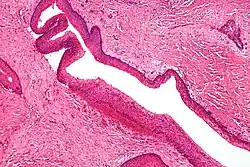

Familial adenomatous polyposis (FAP) is an autosomal dominant syndrome that greatly increases the risk of colorectal cancer. Around 1 in 8000 people will have this disease and it has approximately 100% penetrance. An individual with this disease will have hundreds to thousands of benign adenomas throughout their colon, which will in most cases progress to cancer. Other tumors increased in frequency include; osteomas, adrenal adenomas and carcinomas, thyroid tumors and desmoid tumors. The cause of this disorder is a mutated APC gene, which is involved in β-catenin regulation. Faulty APC causes β-catenin to accumulate in cells and activate transcription factors involved in cell proliferation, migration, differentiation and apoptosis (programmed cell death).[17][18][19]

Nevoid basal cell carcinoma syndrome, also known as Gorlin syndrome, is an autosomal dominant cancer syndrome in which the risk of basal cell carcinoma is very high. The disease is characterized by basal cell nevi, jaw keratocysts and skeletal abnormalities. Estimates of nevoid basal cell carcinoma syndrome prevalence varies, but is approximately 1 in 60000. The presence of basal cell carcinoma is much higher in white than black individuals; 80% and 38%, respectively. Odontogenic keratocysts are found in approximately 75% of individuals with the disease and often occur early in life. The most common skeletal abnormalities occur in the head and face, but other areas are often affected such as the rib cage. The causative genetic mutation of this disease occurs in the PTCH gene, and the product of PTCH is a tumor suppressor involved in cell signaling. Although the exact role of this protein in nevoid basal cell carcinoma syndrome is not known, it is involved in the hedgehog signaling pathway, known to control cell growth and development.[32][33]